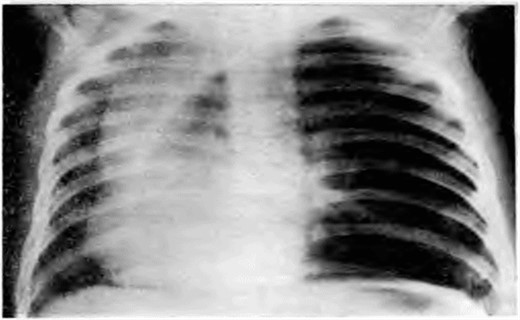

Рентгеновские снимки при врожденной эмфиземе легкого

Раздел: Визуальные уроки